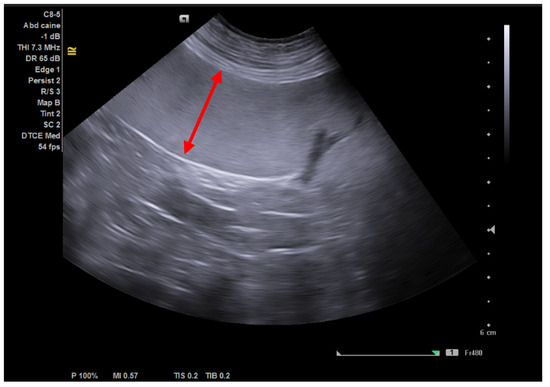

- Hecht, S. Spleen in Atlas of Small Animal Ultrasonography; Penninck, D., d’Anjou, M.A., Eds.; Blackwell Pub.: Ames, IA, USA, 2008; pp. 263–280. ISBN 978-0-8138-2800-8. [Google Scholar]

- Serdean, C.; Dana, C. Ultrasonography of spleen and lymph nodes. In Treatise of Veterinary Clinical Ultrasonography; Codreanu, M.D., Ed.; Medicala: Bucharest, Romania, 2022; pp. 221–236, (In Romanian). ISBN 978-973-39-0931-6. [Google Scholar]